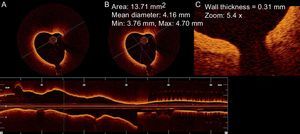

As the valve anatomy was considered suitable for percutaneous intervention, the patient was scheduled a balloon valvuloplasty. The pre-intervention right heart catheterization showed a pulmonary artery pressure of 45/17/29mmHg. After successful mitral dilatation, optical coherence tomography (LightLab Imaging Inc., Westford, Massachusetts, United States) was performed on a distal segmental branch of the right pulmonary artery (Fig. 1).

Optical coherence tomography images showed diffuse thickening of the distal pulmonary arterial wall (Figs. 2 and 3). We registered a pulmonary artery wall thickness between 0.28mm and 0.31mm, higher when compared to reports from subjects without pulmonary hypertension (0.16 [0.03] mm for vessels with 2.14 [0.33] mm of diameter). No complications arose during or after the procedure.